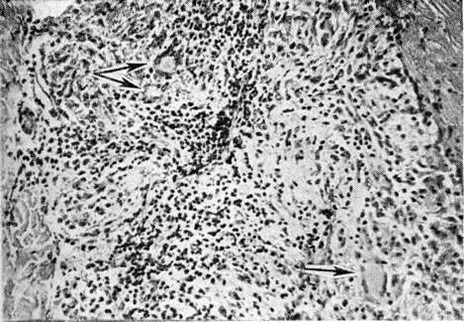

Основным способом размножения микобактерий Лепра является деление материнской клетки и врастания поперечной перегородки. Микобактерия Лепра является облигатным внутриклеточным паразитом тканевых макрофагов или клеток ретикулоэндотелиальной системы, проявляет выраженный тропизм к коже и периферическим нервам, но на поздних стадиях развития процесса встречается также во многих других клетках и тканях организма. В тканевой клетке микобактерии Лепра размножаются только в цитоплазме (рисунок 4); внутриядерный паразитизм для них нехарактерен. Микобактерии в лепрозных клетках иногда отграничены от цитоплазмы клетки-хозяина фагосомной мембраной. На поздних стадиях инфекции паразитирование возбудителей Лепра человека сопровождается нарушением строения эндоплазматического ретикулума и митохондрий клетки-хозяина.

Гистологически лепроматозный тип характеризуется лепроматозной гранулемой кожи, которая представляет инфильтрат, расположенный в сетчатом слое, отделённый от эпидермиса непоражённой зоной коллагеновой ткани. Основными клеточными элементами лепроматозной гранулемы являются лепрозные клетки; кроме того, наблюдаются отдельные плазматические, лимфоидные клетки, единичные фибробласты, многоядерные пенистые клетки (цветной рисунок 1—6). Лепрозные клетки относятся к макрофагам, характеризуются бледным ядром и «пенистой» цитоплазмой (рисунок 5) за счёт содержания липидов. Лепрозный макрофаг на ранних стадиях содержит жирные кислоты, фосфолипиды, ненасыщенные липиды; на стадии развития процесса преобладают нейтральные жиры и кислотные липиды. Большинство исследователей считает, что основная масса липидов представляет собой продукт метаболизма и распада микобактерий Лепра. Наиболее характерная особенность лепрозного макрофага — нахождение и размножение в нем большого количества микобактерий Лепра, то есть явление незавершённого фагоцитоза (смотри полный свод знаний). В цитоплазме лепрозной клетки выявляется высокий уровень окислительно-восстановительных ферментов, кислой фосфатазы, неспецифической эстеразы и не обнаруживается активность липазы. Для гистологический картины LL характерно также наличие капилляров со значительным сужением их просвета за счёт пролиферации и набухания эндотелиальных клеток, содержащих большое количество микобактерий типа «глоби». Кожные нервы пронизаны инфильтратами из микробосодержащих клеток (цветной рисунок 7 и 10). Микобактерии обнаруживаются также в клетках эндоневрия. В лепроматозных поражениях большой давности отмечается частичное или полное разрушение придатков кожи (фолликулов волос, сальных и потовых желёз).

Для Лепра характерно поражение периферической нервной системы. Микобактерии обнаруживаются практически во всех участках нервных волокон. При лепроматозном типе инфильтрат состоит из пенистых макрофагов, при туберкулоидном — из эпителиоидных клеток. Отмечается более быстрое развитие воспаления при туберкулоидном типе, чем объясняется раннее появление неврологический нарушений. При лепроматозном типе Лепра происходит постепенное замещение нервного волокна соединительной тканью. Лепрозный неврит, как правило, имеет восходящий характер. Отмечается наиболее частое поражение чувствительных нервов и выраженный тропизм микобактерий Лепра к леммоцитам (шванновским клеткам).

Поражение внутренних органов наиболее выражено при лепроматозном типе Лепра Специфические изменения в виде гранулем из макрофагов с высоким содержанием микобактерий обнаруживаются в печени (цветной рисунок 11), селезёнке, костном мозге, слизистой оболочке верхних дыхательных путей, яичках, надпочечниках, лимфатических, узлах. В материале, полученном при пункции периферических лимфатических, узлов, обнаруживаются микобактерии Лепра; в паракортикальной области выявляются скопления недифференцированных макрофагов, содержащих большое количество микобактерий; зародышевые центры хорошо развиты, а мозговые тяжи заполнены плазматическими клетками.